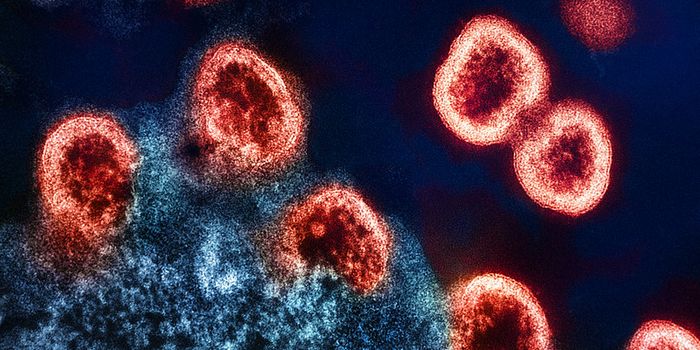

SEP 08, 2024MicrobiologySARS-CoV-2, the pandemic virus that causes COVID-19, has mutated endlessly since it burst on the scene in late 2019. An ...

AUG 27, 2024MicrobiologySince the start of the COVID-19 pandemic, the virus that causes the illness - SARS-CoV-2 - has had a practically infinit ...